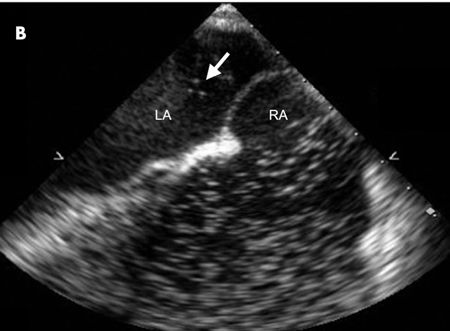

A CT scan of the chest revealed large bilateral pulmonary emboli. A heparin weight-based protocol was started, and transthoracic echocardiography was performed to look for signs of right heart strain. The imaging revealed what appeared to be 2 large echodense structures within the left and right atria. A follow-up transesophageal echocardiography (TEE) revealed a large mobile echogenic structure of 3.6 X 1.5 cm traversing the intra-atrial septum at the level of the foramen ovale, consistent with a thrombus-in-transit (A). During the procedure, the patient began retching and repeated viewing of the intra-atrial septum revealed that the thrombus had completely disappeared. An agitated saline study showed contrast bubbles passing from the right atrium (RA) to the left atrium (LA), confirming the presence of a patent foramen ovale (B).

Intracardiac thrombi are most often associated with pulmonary emboli and can be visualized on transthoracic or transesophageal echocardiography in as many as 4% to 18% of cases.1 If a patent foramen ovale is present, a thrombus can cross from the right atrial circulation directly into the left atrium. When the thrombus is not attached to any other intracardiac structure, the phenomenon is known as a thrombus-in-transit.2